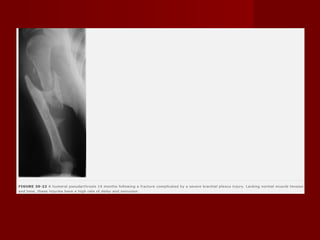

Lesões associadas a fraturas de úmero Paralisia do nervo Radial Nervo mais comum a ser lesado Geralmente ocorre uma neuropraxia, com retorno espontâneo da função.  Geralmente ocorre devido contusão/alongamento no momento de uma fratura em espiral Depende da energia do trauma, pode variar de 3 a 34% aumentando em fraturas expostas, politrauma, lesão vascular. Não é uma indicação de exploração Indicações de exploração quando há uma lesão exposta ou lesão ipsilateral e for necessário cirurgia aberta. Primeira indicação prognóstico, se o nervo estiver lesado indica uma ráfia, segunda o nervo pode estar interpondo o foco da fratura ou qualquer outro tipo de compressão do nervo. Se apresentar paralisia orientar o paciente utilizar uma imobilização para manter o punho em extensão e fazer movimentação passiva do punho e dos dedos para evitar contratura em flexão

Eletroneuromiografia 3 semanas pos lesão Observar qualquer sinal de recuperação do nervo geralmente no músculos distais a lesão braquiradial, o extensor radial curto e longo do carpo Se não ocorrer nenhum sinal de recuperação em 3 ou 4 meses, exploração do nervo é indicada

Lesões associadas afraturas de úmero Paralisia do nervo Radial Nervo mais comum a ser lesado Geralmente ocorre uma neuropraxia, com retorno espontâneo da função. Geralmente ocorre devido contusão/alongamento no momento de uma fratura em espiral Depende da energia do trauma, pode variar de 3 a 34% aumentando em fraturas expostas, politrauma, lesão vascular. Não é uma indicação de exploração Indicações de exploração quando há uma lesão exposta ou lesão ipsilateral e for necessário cirurgia aberta. Primeira indicação prognóstico, se o nervo estiver lesado indica uma ráfia, segunda o nervo pode estar interpondo o foco da fratura ou qualquer outro tipo de compressão do nervo. Se apresentar paralisia orientar o paciente utilizar uma imobilização para manter o punho em extensão e fazer movimentação passiva do punho e dos dedos para evitar contratura em flexão

Eletroneuromiografia 3 semanaspos lesão Observar qualquer sinal de recuperação do nervo geralmente no músculos distais a lesão braquiradial, o extensor radial curto e longo do carpo Se não ocorrer nenhum sinal de recuperação em 3 ou 4 meses, exploração do nervo é indicada